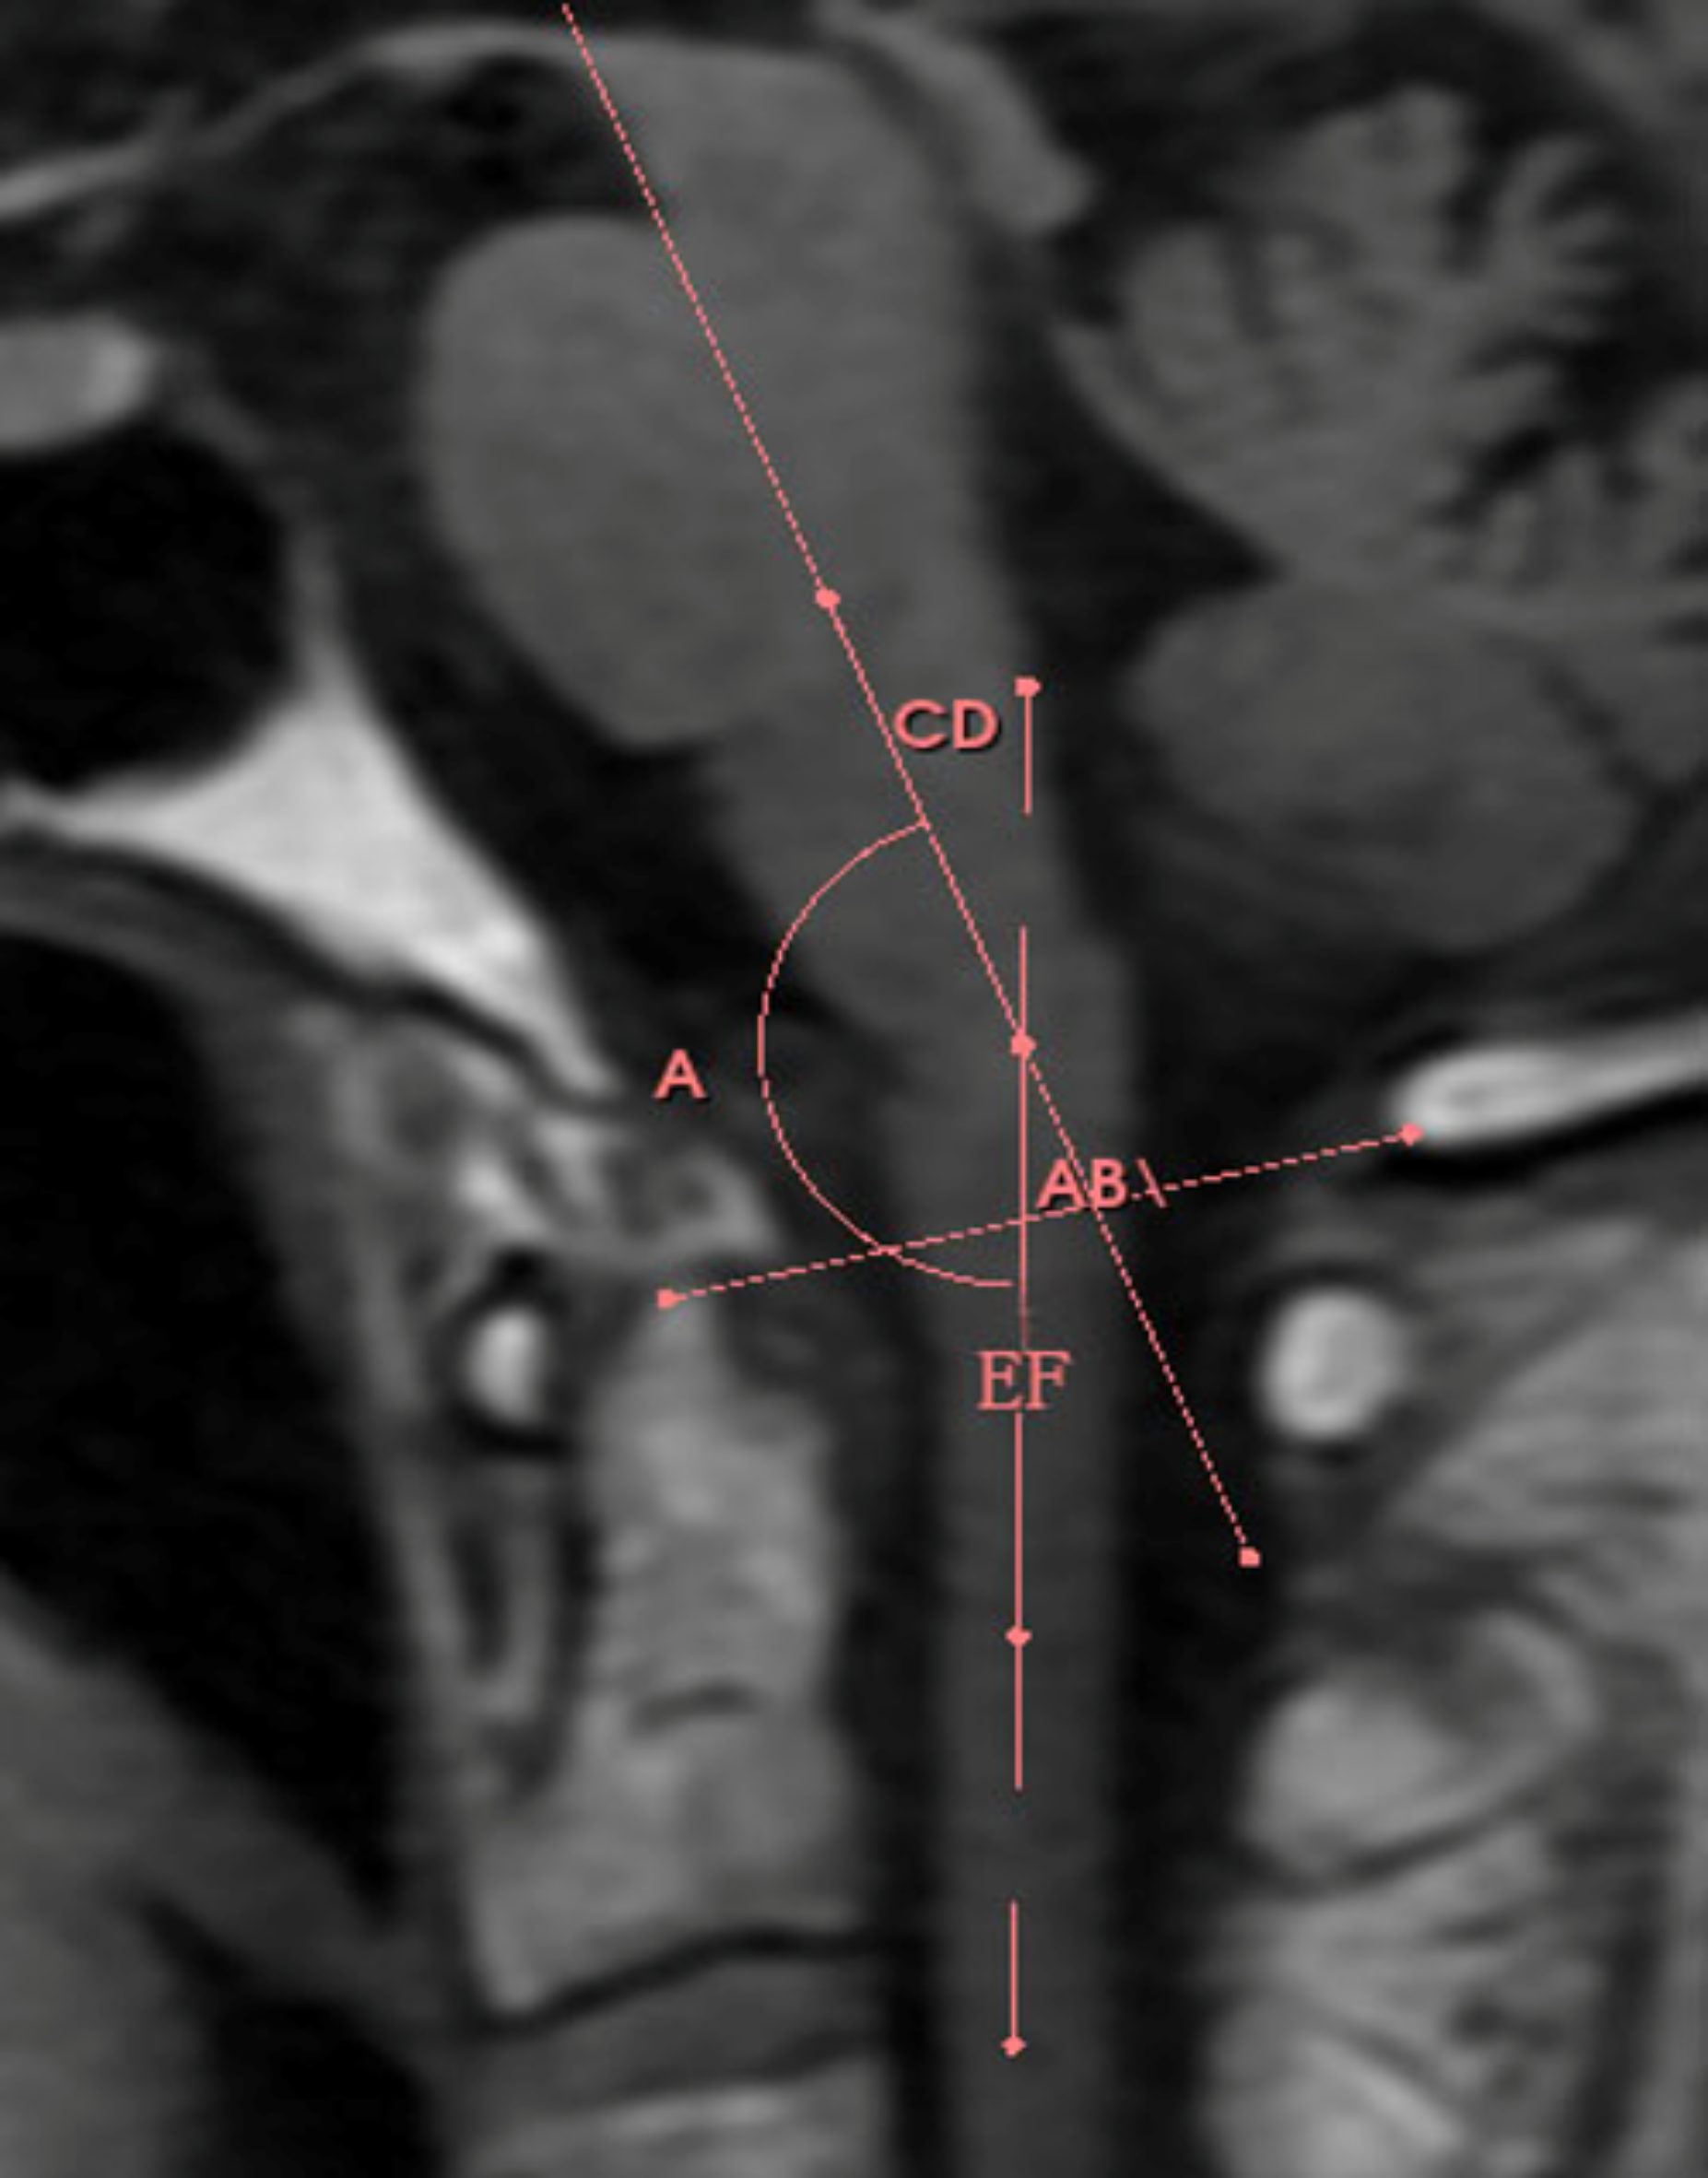

Fig. 3

Diagram of pons–medulla angle. AB line: Line of the foramen magnum; CD line: Midsagittal axis of brainstem; EF line: Midsagittal axis of spinal cord; Angle A: Angle at CD-EF intersection.